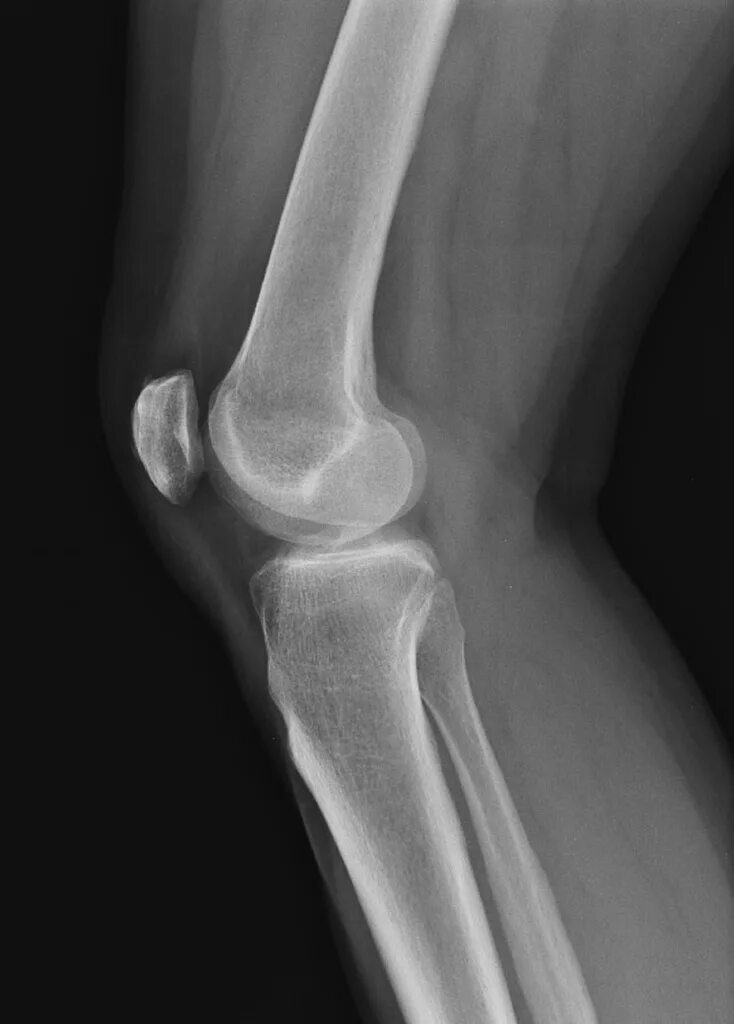

Как выглядит коленного